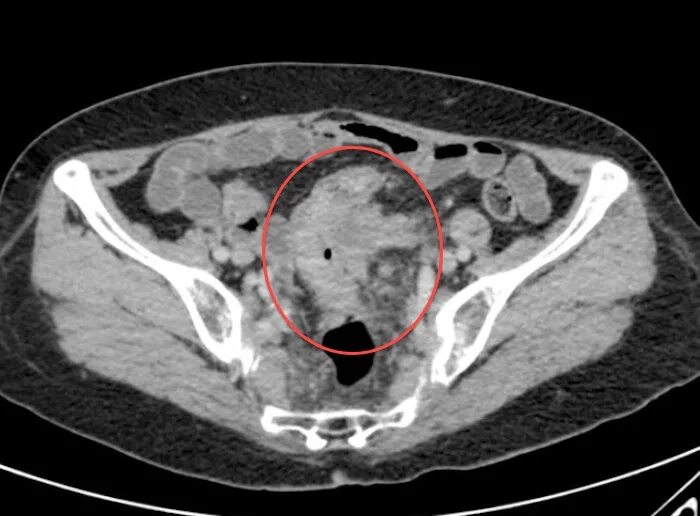

Метастазы при раке сигмовидной кишки